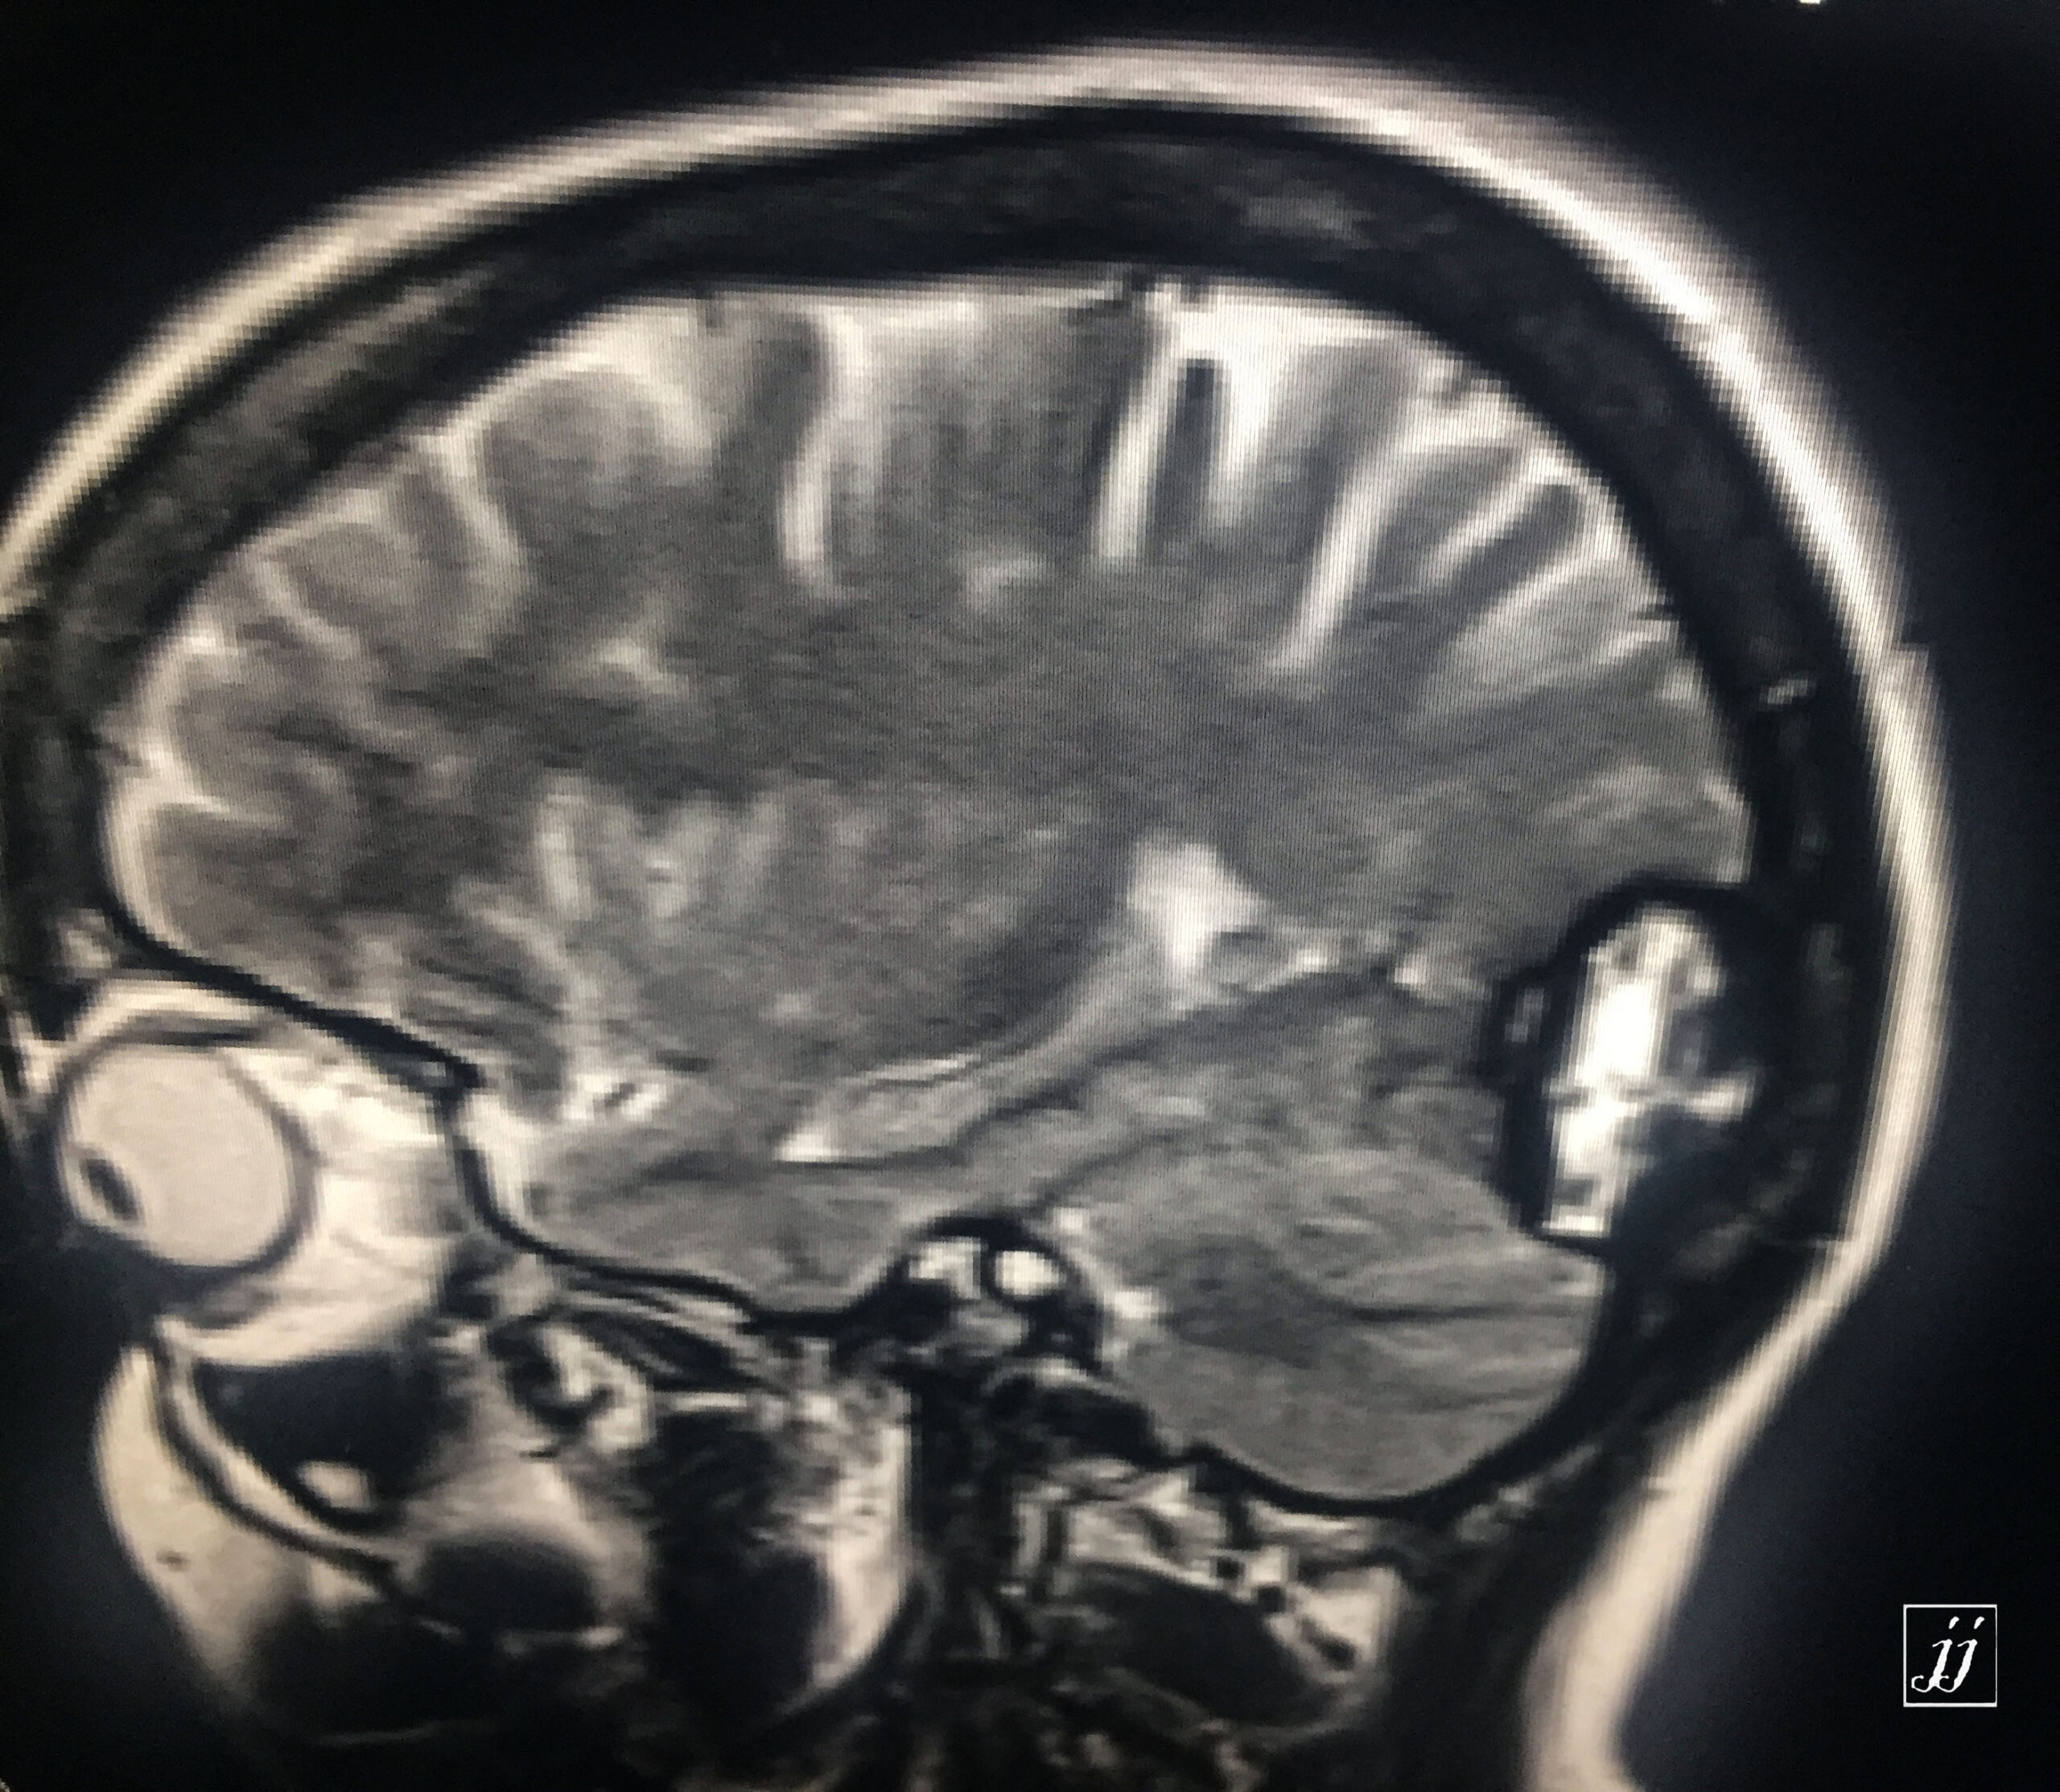

Brain- right posterior parietal old hematoma (6)